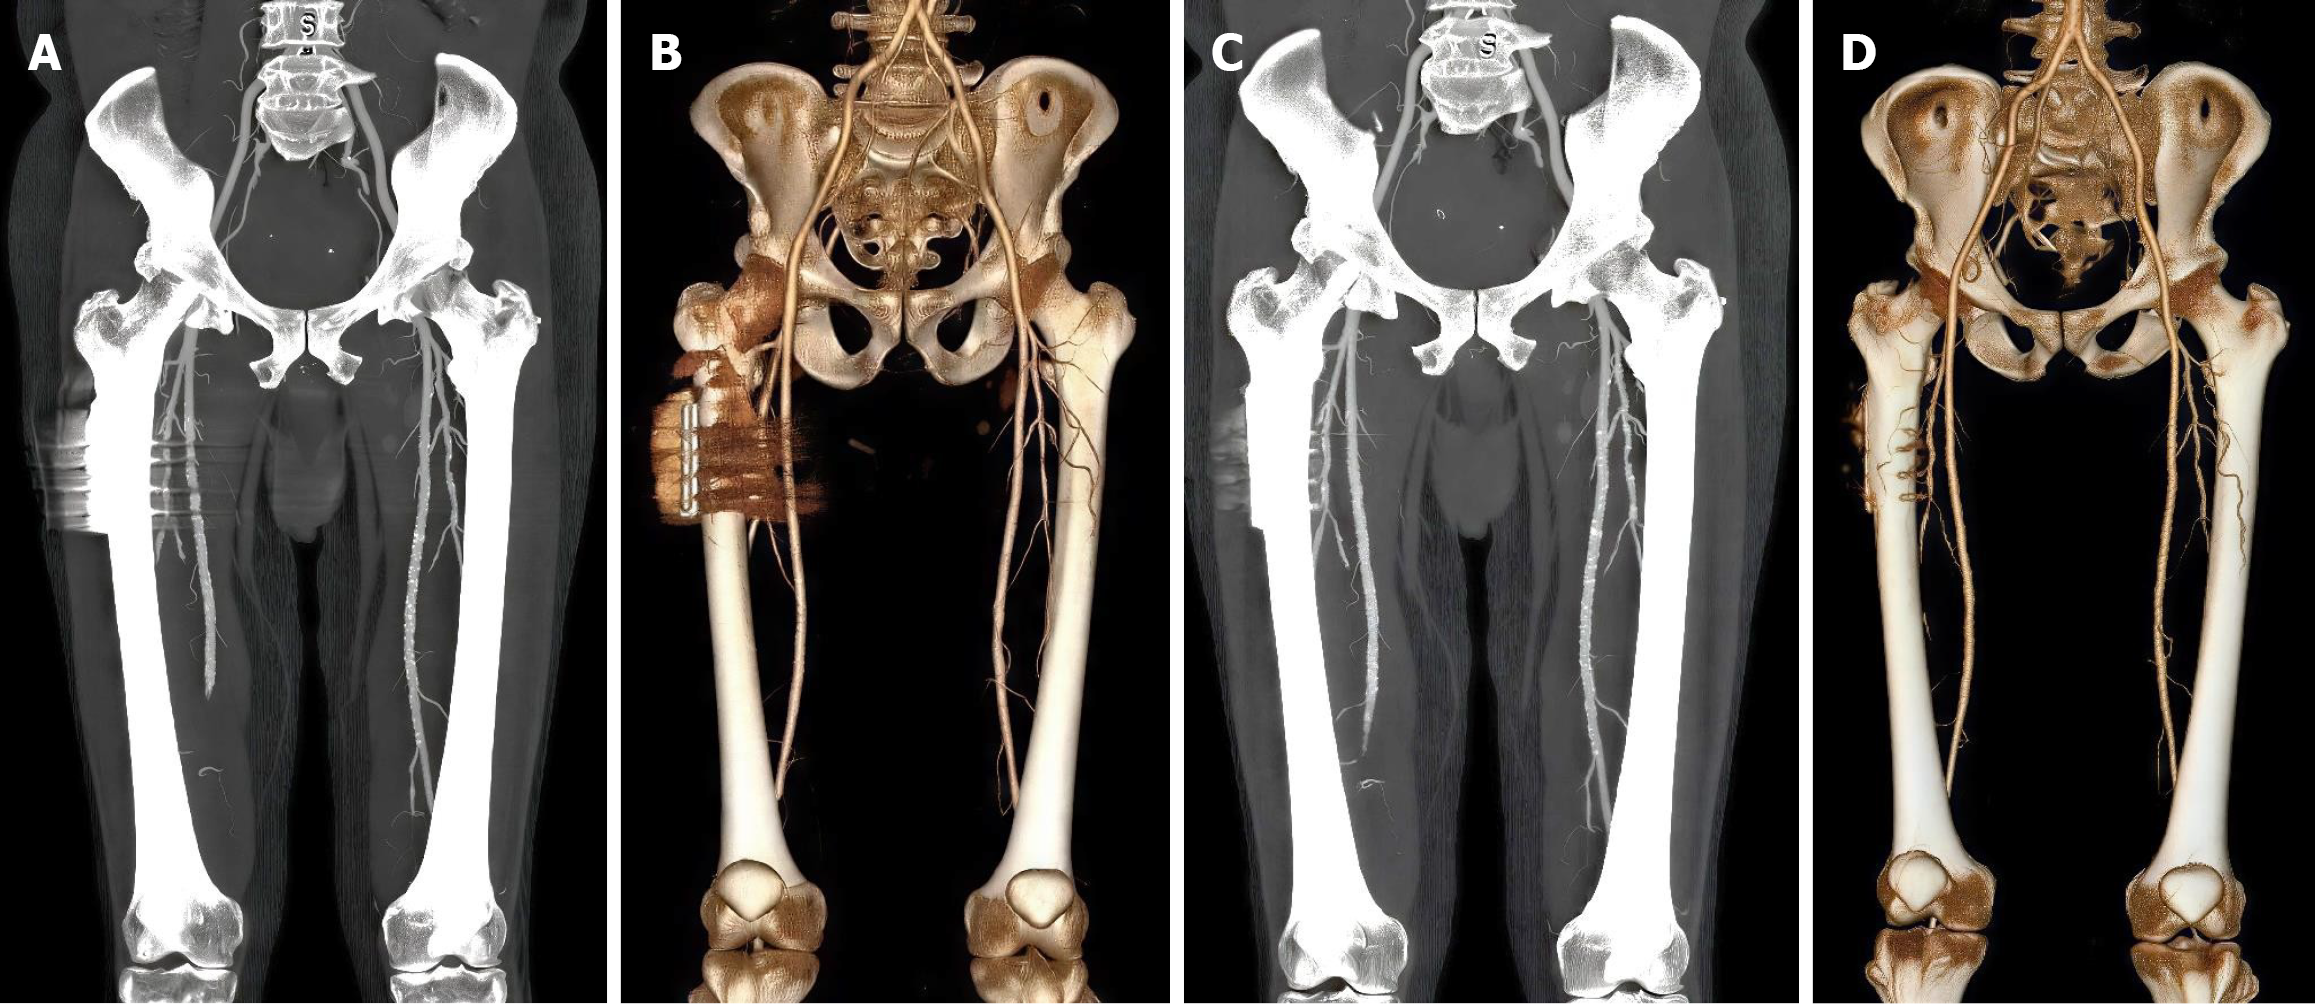

Case 2: 58-year-old male with history of right femoral neck fracture treated with open reduction and internal fixation using dynamic hip screw. Patient presented with claudication symptoms and underwent lower limb CTA to assess for atherosclerotic disease affecting the right lower extremity (Figure 2).

Figure 2

Figure 2  Metal artifact reduction in iliofemoral computed tomography angiography: A comparative visualization. A and B: Pre-metal artifact reduction (MAR), coronal reformatted computed tomography angiography maximum intensity projection and volume rendering images at ilio-femoral level without MAR showing artifact-induced degradation of image quality and pseudo-stenoses at right superficial femoral and profunda femoris arteries; C and D: Post-MAR, same reformats with single-energy MAR reconstruction shows significant artifact reduction and clear visualization of femoral arteries.